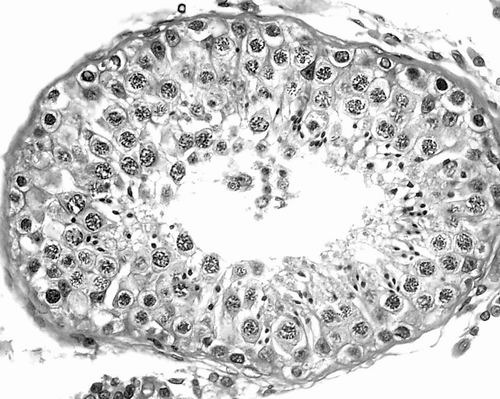

图为人类精母细胞。A为同源染色体配对联会正常的精母细胞;B为同源染色体配对联会异常的精母细胞。